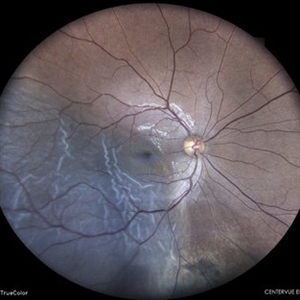

PROLIFERATIVE DIABETIC RETINOPATHY

COLOUR FUNDUS PHOTOGRAPH OF A 50 YEAR OLD MALE WITH PROLIFERATIVE DIABETIC RETINOPATHY

Photographer: Dr. Akansha Sharma-Retina Foundation, Ahmedabad

Condition/keywords: florid type PDR, proliferative diabetic retinopathy (PDR)